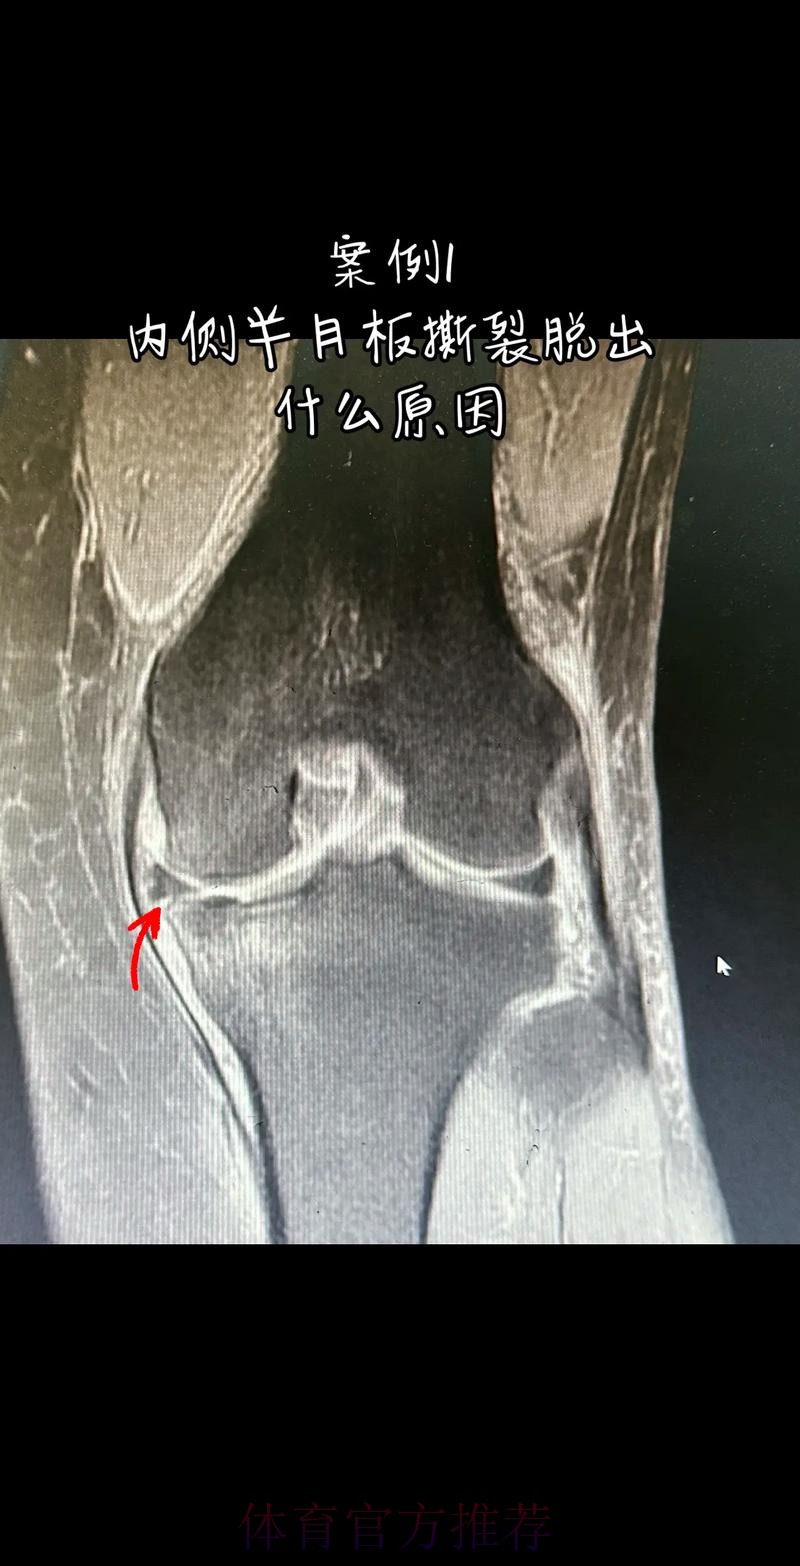

从医学角度看 半月板是膝关节内一块呈“C”形的软骨结构 其作用是缓冲冲击 稳定膝关节 并帮助分散压力 “左膝内侧半月板撕裂”通常说明在一次急停 旋转 或对抗中 半月板受到了超过其承受极限的力导致结构损伤 这类伤病常见于足球 篮球等需要频繁变向和对抗的项目 对于职业球员而言 半月板损伤严重程度不一 但共同点是都会影响支撑发力 跳跃以及变向时的稳定性 而官方给出的“预计伤缺6-8周”这个时间区间 往往对应的是中度损伤或通过微创手术加积极康复能够较快回归的情况 也意味着暂时没有出现必须长时间休战的最坏结果

这条“官方 阿拉巴左膝内侧半月板撕裂 预计伤缺6-8周”的声明一出 不只是伤病通告那么简单 它背后牵动的是皇马后防体系的重塑 奥地利国家队备战计划的调整 以及一名顶级后卫职业生涯中一次关键的健康考验 对于已经习惯在高强度赛程中同时承担俱乐部与国家队重任的阿拉巴来说 这次伤病既是一次身体的警报 也是一次心理与战术层面的巨大挑战

在现代足球中 像阿拉巴这样能胜任中卫 左后卫 甚至后腰的多面手几乎是教练心中最理想的拼图 他不仅是后场的防守屏障 更是从后场发起进攻的节拍器 因此 当“左膝内侧半月板撕裂 伤缺6-8周”这样的诊断从官方口中给出时 对球队来说 就等同于在关键路段突然失去一块核心路基 球迷最直观的担忧是 皇马在这段时间是否还能保持防线稳定 奥地利是否在国际比赛日期间陷入被动 而对阿拉巴本人而言 这则官方消息意味着一个不得不按下暂停键的阶段 他需要重新面对恢复训练 康复计划 以及未来的竞技状态